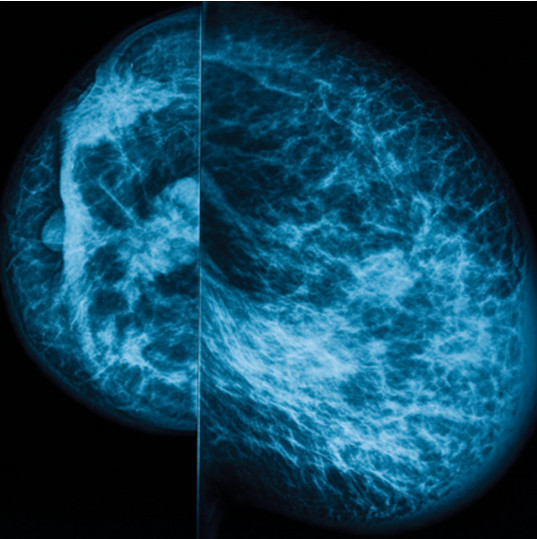

UCSF Breast Imaging delivers an expert overview of clinically relevant continuing medical education topics. Through didactic lectures, challenging case presentations, and faculty Q&A sessions, speakers highlight the latest developments, sharply focusing on the use of multimodality imaging and intervention (mammography, ultrasound and MRI).